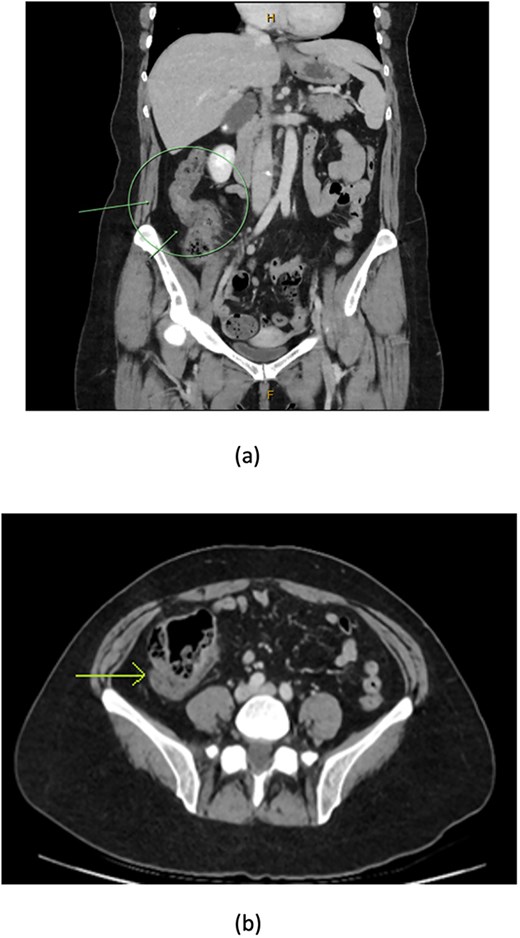

A 48-year-old lady with a background history of chronic migraines and family history of Crohn’s Disease presented to the emergency department with a three-day history of worsening abdominal pain and obstipation. She underwent a colonoscopy three days prior, which demonstrated shallow ulceration in the rectum and distal colon as well as a web-like stenosis in the ascending colon, 60 cm from the anal verge. The stenotic region was <5 mm in size and was unable to be traversed by the colonoscope, suspicious for a newly diagnosed stricturing Crohn’s disease (Fig. 1). She admitted to taking indomethacin suppositories 100 mg daily over the last two years for her migraines, as well as propranolol, triptan, ondansetron and sertraline. On examination her abdomen was soft, and tender in the right paraumbilical region without peritonism. Her haemoglobin was 94 g/L (115–165 g/L), C reactive protein (CRP) demonstrated a moderate inflammatory process at 40 mg/L (< 5 mg/L). Serum biochemistry and white cells were within normal limits. Computed tomography (CT) demonstrated a stricture in the ascending colon with an evolving proximal large bowel obstruction (Fig. 2). There was faecalisation in the terminal ileum suggestive of an acute on chronic obstruction. There was no suggestion of gastrointestinal perforation, or metastatic disease. The patient was made nil by mouth and prescribed intravenous hydrocortisone 100 milligrams four times a day by the gastroenterologist for suspected Crohn’s disease. However, the patient failed to progress after four days of hydrocortisone. A colonoscopic balloon dilatation was attempted with a 6 mm balloon, however the stricture appeared well-established, and the site began to bleed after the first attempt (Fig. 3). Subsequent attempts were abandoned due to the risk of bowel perforation. The distal end of the stricture was tattooed using spot ink. A colorectal surgeon became involved in her care who recommended a laparoscopic right hemicolectomy.

CT coronal (a) and axial (b) views showing thickening of the ascending colon (arrows) with faecalised and distended distal ileum.